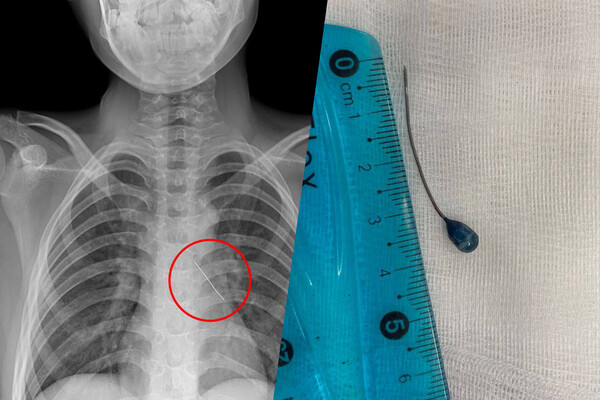

При поступлении в больницу подросток мог говорить только шепотом и жаловался на сильные боли в груди. Рентген показал, что инородное тело находится в области нижней доли левого бронха. Вокруг булавки скопилась мокрота, а острый конец пронзил стенку бронха — это могло привести к коллапсу легкого.

Врачи отделения реконструктивной хирургии провели малоинвазивную операцию. Через эндоскоп они удалили скопления слизи, обнаружили колпачок французской булавки и с помощью оптических щипцов аккуратно извлекли инородное тело. Кровотечение было минимальным и остановилось самостоятельно. Через три дня мальчика выписали под наблюдение врачей по месту жительства.